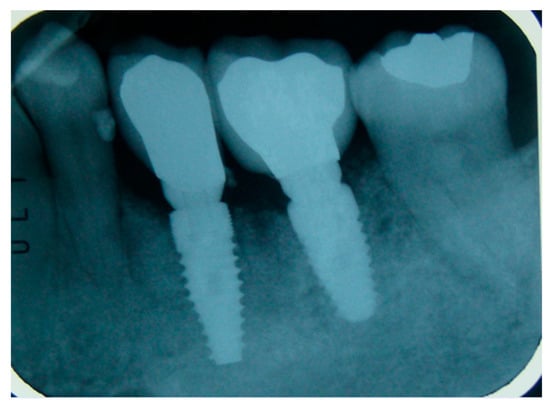

Figure 5. X-ray after 30 months of follow up showing the implant with the prosthesis.